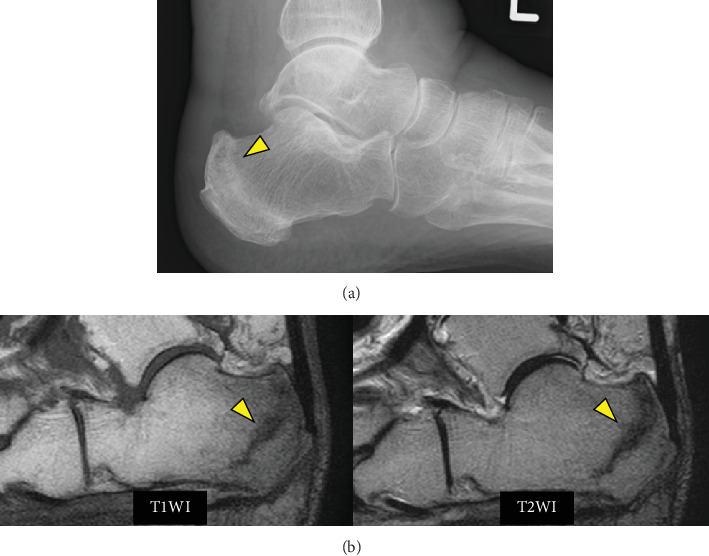

Herein, we present a rare case of periprosthetic joint infection (PJI) which was triggered by an infection with a latent subcutaneous cyst on the thigh and occurred in a strange course following total knee arthroplasty (TKA). An 87-year-old female underwent right TKA followed by left TKA 5 months later. Six weeks after left TKA, a painful subcutaneous induration appeared in the left medial thigh. Magnetic resonance imaging revealed a 30∗50-mm multifocal mass. The cystic fluid was brown and cloudy, indicating an infected cyst. Oral antimicrobial therapy was initiated for 7 days. Nine weeks after the left TKA, a left calcaneal fracture occurred. Subsequently, edema of the lower extremities and pain in the left knee gradually developed. Arthrocentesis was performed twice: joint fluid Gram staining and culture examination were negative. However, at 12.5 weeks, an alpha-defensin test of the synovial fluid was positive. Therefore, PJI was diagnosed. DAIR was performed, followed by multiantibiotic therapy. The infection subsided gradually. Edema of the lower limbs was treated with oral diuretics, lymphatic massage, and compression stockings. Consequently, the lower limb edema also improved. In this case, infection of a latent subcutaneous cyst in the thigh occurred and spread around the prosthesis due to leg edema, which was associated with loss of lower limb motion due to a calcaneal fracture. The presence of a potential thigh subcutaneous cyst is a risk factor for PJI. Moreover, lower extremity edema occurs by decreasing lower extremity motion, such as after a calcaneal fracture, and it increases the risk of extending extra-articular infection to the PJI. Potential thigh subcutaneous cysts and lower extremity edema are risk factors for the development of PJI. Orthopedic surgeons need to be aware of these facts during follow-up after TKA.

在此,我们报告一例罕见的假体周围关节感染(PJI),其由大腿上潜伏的皮下囊肿感染引发,发生在全膝关节置换术(TKA)后的奇怪过程中。87岁女性,5个月后行右侧TKA,左侧TKA。左侧TKA术后6周,左侧大腿内侧出现疼痛的皮下硬化。磁共振成像显示一个30 * 50毫米的多灶性肿块。囊性液体呈棕色浑浊,表明囊肿感染。开始口服抗菌药物治疗7天。左侧TKA术后9周,发生左侧跟骨骨折。随后,下肢水肿和左膝疼痛逐渐加重。关节穿刺2次,关节液革兰氏染色及培养检查阴性。然而,在12.5周时,滑液α -防御素测试呈阳性。因此诊断为PJI。进行DAIR,然后进行多种抗生素治疗。感染逐渐消退。下肢水肿用口服利尿剂、淋巴按摩和加压袜治疗。因此,下肢水肿也得到改善。在这个病例中,由于腿部水肿,大腿潜伏的皮下囊肿发生感染,并在假体周围扩散,这与跟骨骨折导致的下肢运动丧失有关。潜在的大腿皮下囊肿的存在是PJI的危险因素。此外,下肢水肿是由于下肢运动减少而发生的,如跟骨骨折后,这增加了关节外感染扩展到PJI的风险。潜在的大腿皮下囊肿和下肢水肿是PJI发展的危险因素。骨科医生在TKA后的随访中需要了解这些事实。